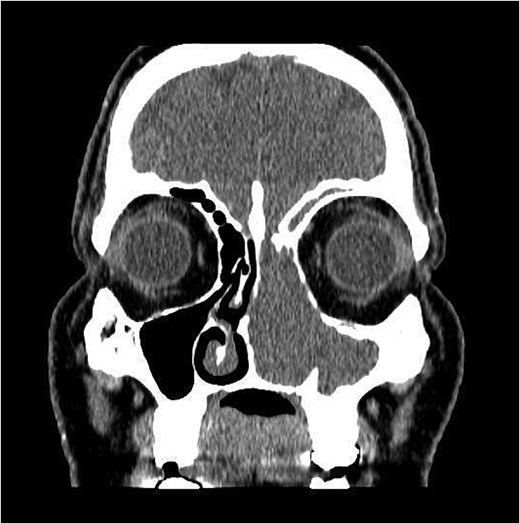

CT showed a heterogeneously enhancing mass completely occluding the left nasal cavity, left ethmoidal, maxillary and frontal sinuses, extending to left pterygopalatine fossa. It is associated with bony erosion of the posterior nasal septum and the left medial maxillary wall (Figs 1 and 2). Findings were suggestive of inverted papilloma vs sinonasal malignancy. Therefore, biopsy was recommended.

Coronal section of CT paranasal sinus with contrast soft tissue window showing the mass occupying the left nasal cavity and extending to maxillary and ethmoidal sinus.

Coronal section of CT paranasal sinus soft tissue window showing the mass occupying the left nasal cavity and extending to maxillary and ethmoidal sinus, and reaching base of skull.

Coronal section of CT paranasal sinus bone window showing bony erosions of nasal septum, maxillary wall, lamina papyracea, and cribriform plate.